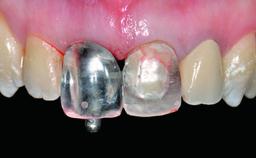

| Abutment Type | CAD/CAM |

| Prosthesis Type | FDP |